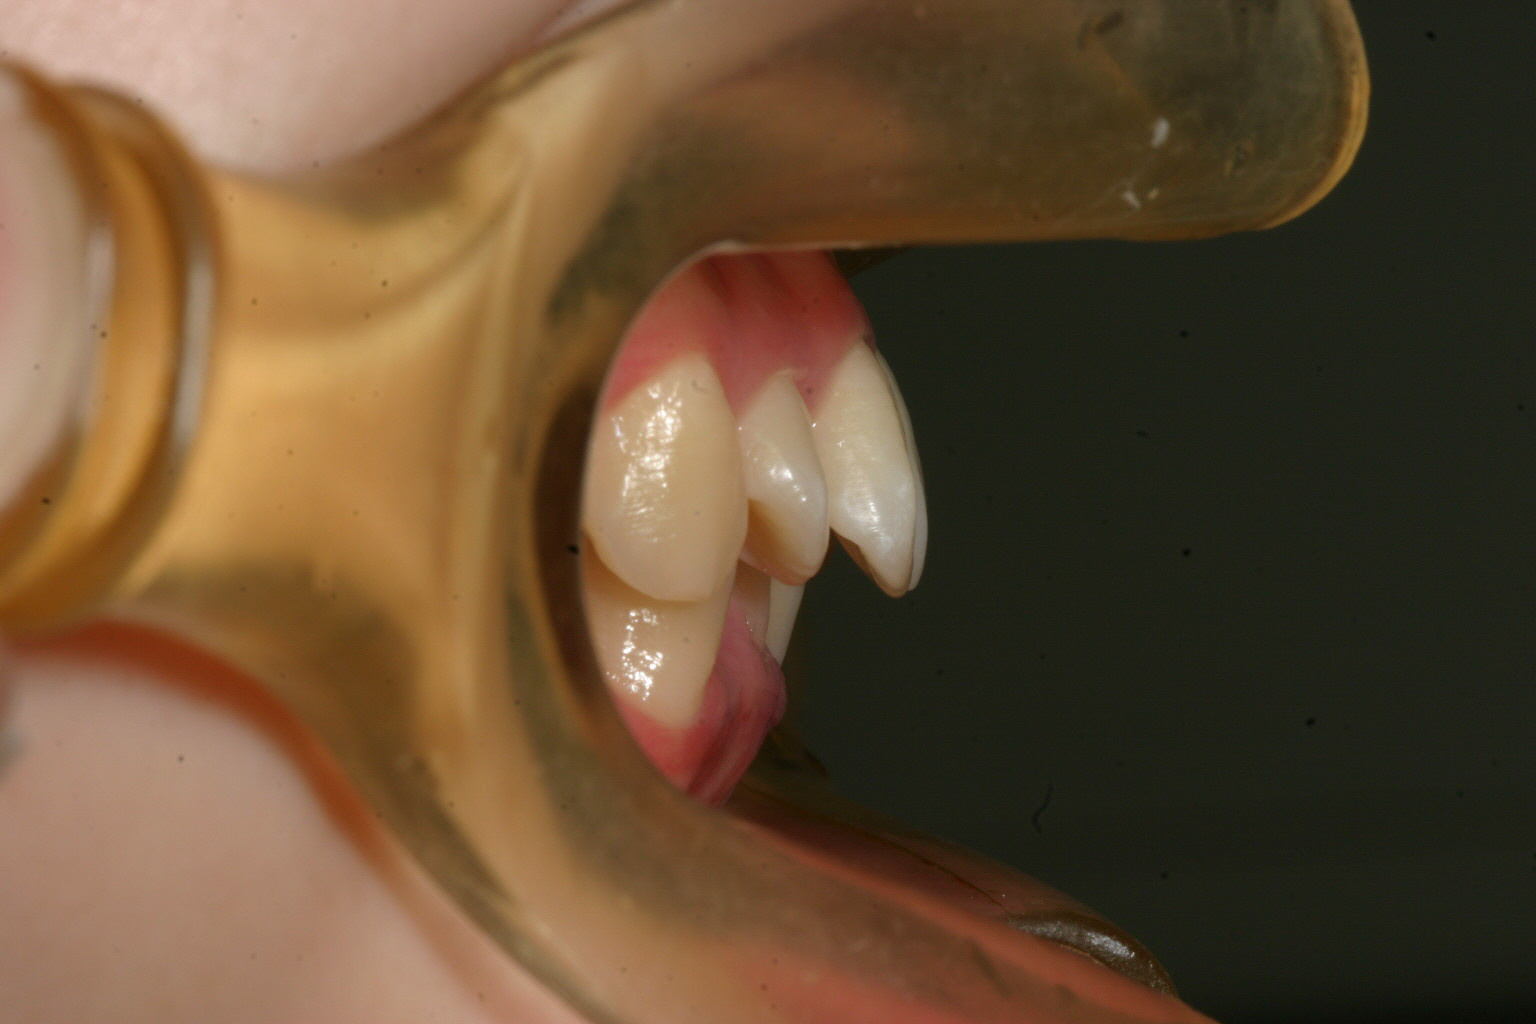

横から見た出加減です。

術前と比較するとかなり入りましたね!